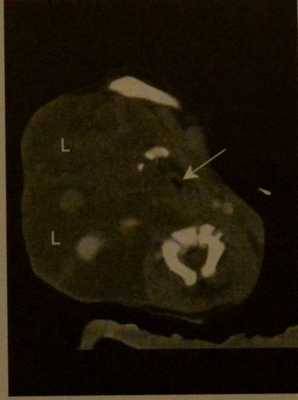

Контрастная КТ. Лучшая визуализация распространения лимфангиомы и определение наличия кровоизлияния. Опухоль распространяется в окологлоточную и заглоточную области, смещает и сдавливает верхние дыхательные пути (стрелка).